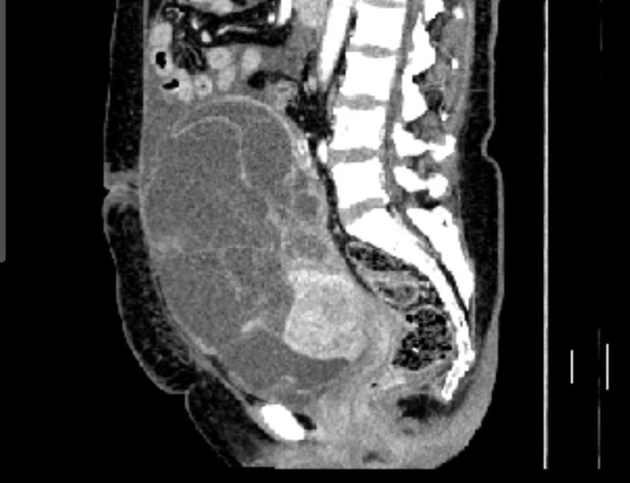

2019年7月16日,术后腹部CT

2019-06-27 复查CT示:1. 左半结肠+右侧附件切除术后;2.肝内多发转移瘤并消融术后改变。